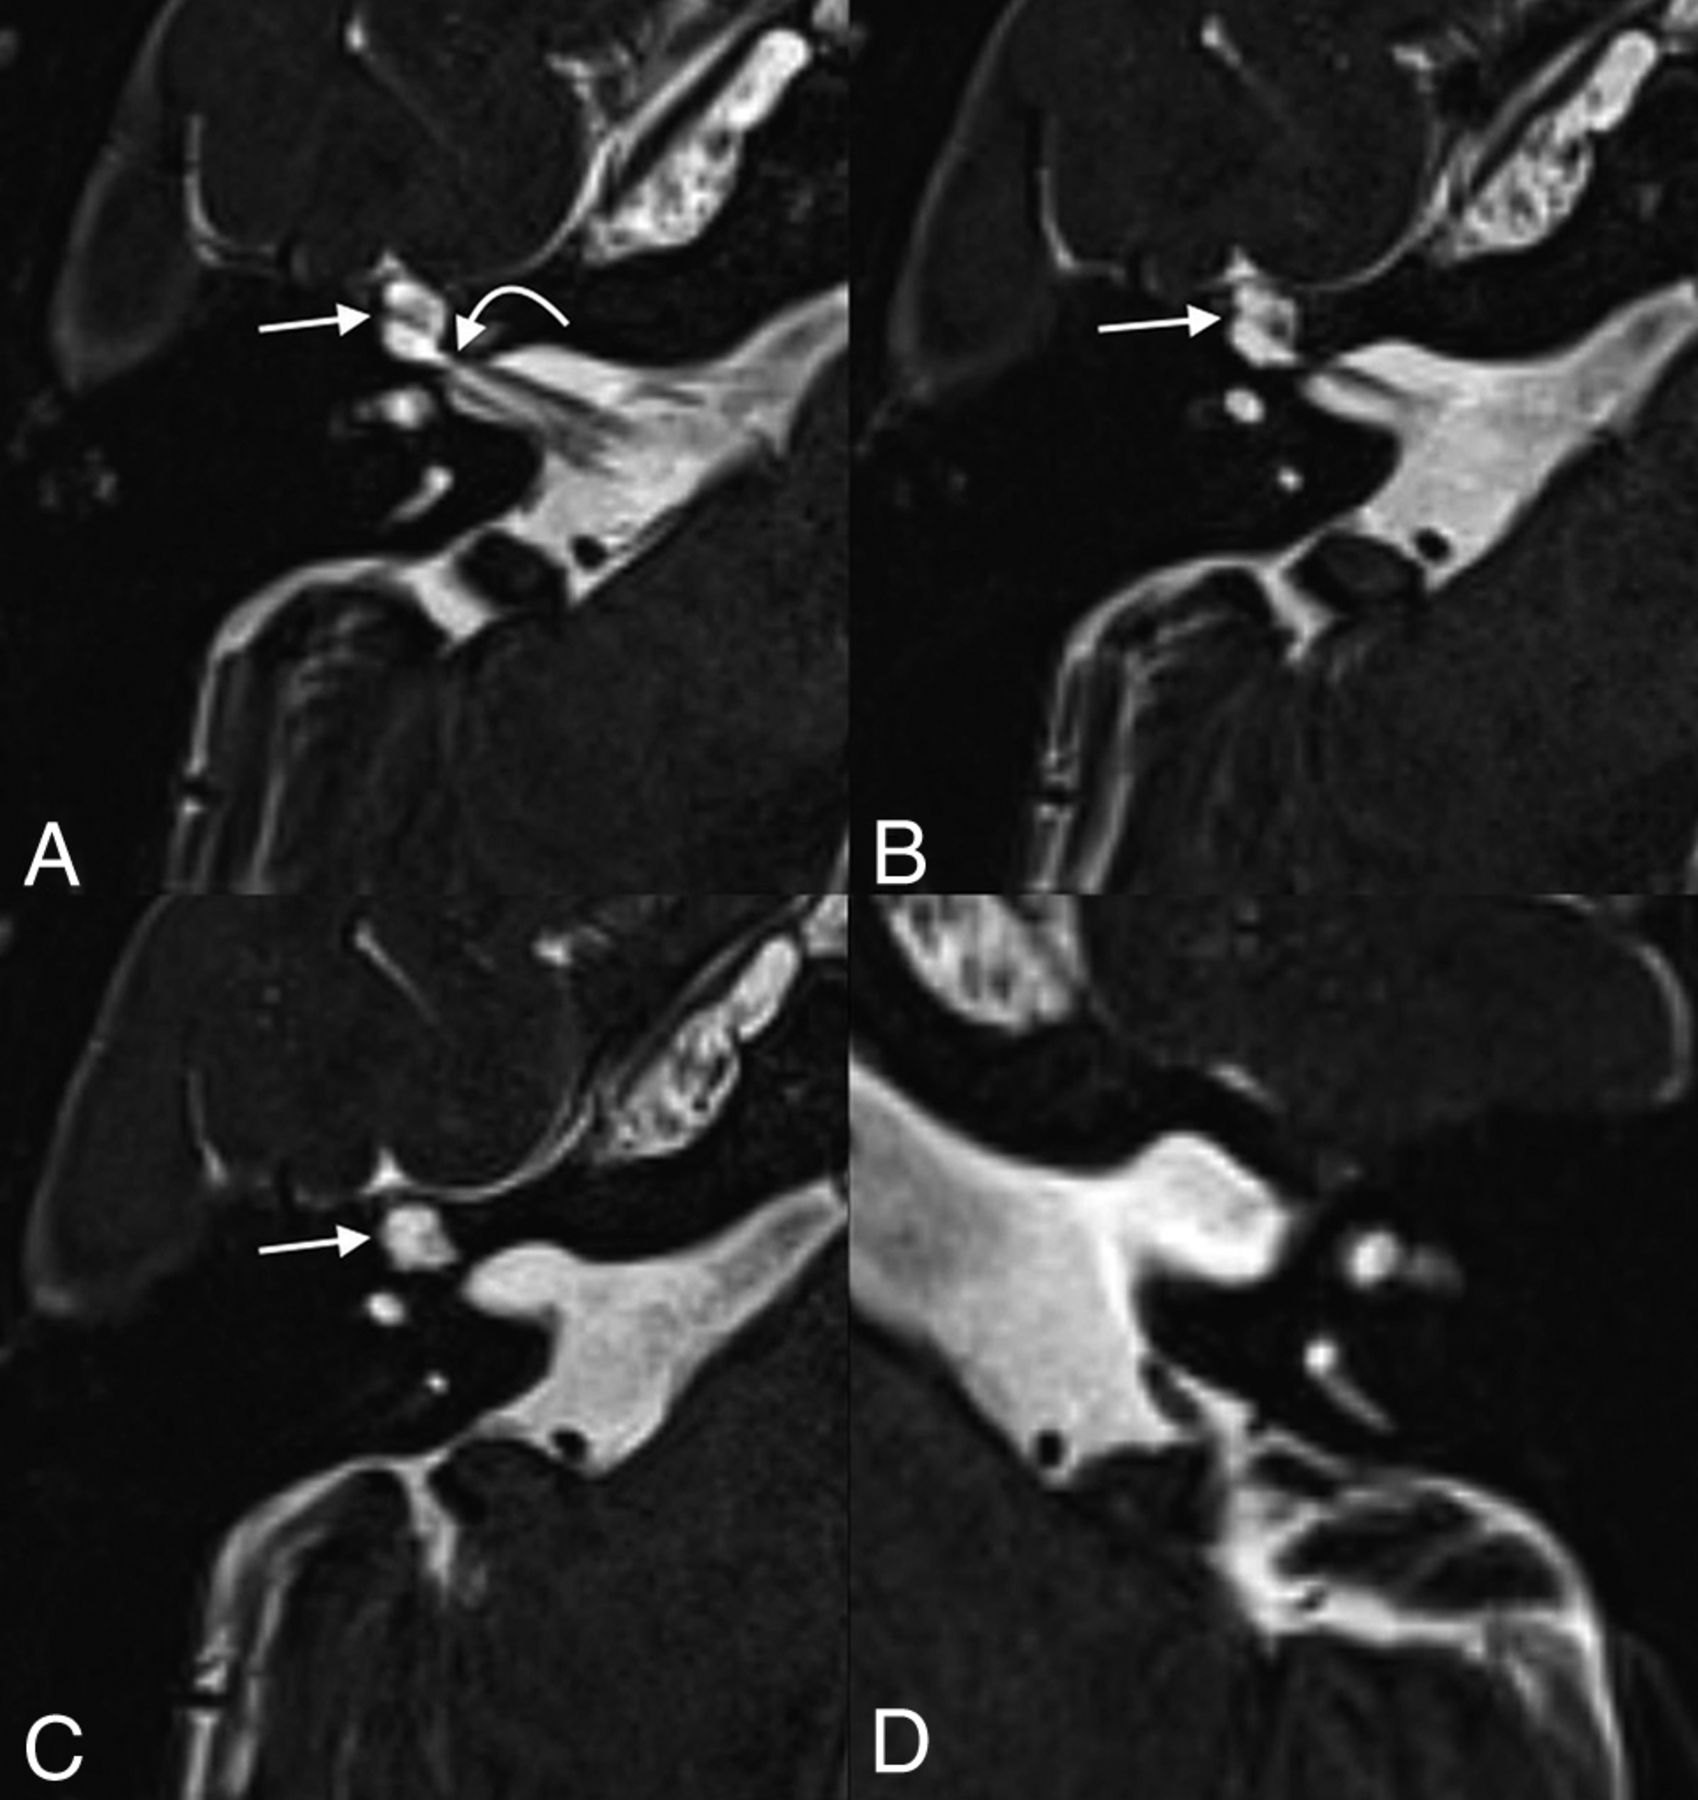

A 45-year-old woman who underwent imaging to follow up a known right vestibular schwannoma. Axial T2 SPACE images demonstrate fluid within the geniculate ganglion of the left facial nerve canal, with dilation measuring up to 2.7 mm, compatible with a meningocele (long arrows, A and B). Fluid is also seen tracking along the expected course of the proximal left greater superficial petrosal nerve (short arrow, B). The known vestibular schwannoma is seen in the contralateral right internal auditory canal, extending through the porus acusticus (curved arrow, C).